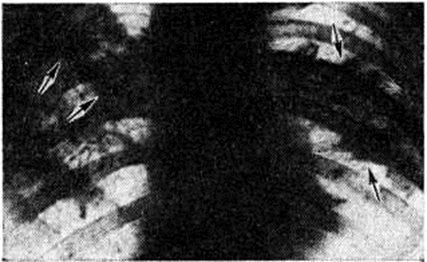

Рентгенологическая картина при Пневмокониозы зависит не только от степени фиброзных изменений в лёгких, но и от рентгеноконтрастности самой пыли, вдыхание которой вызывает развитие фиброза лёгочной ткани. При оценке рентгенологической картины принимается во внимание величина затемнений, их форма, контуры, плотность, площадь распространения. По характеру изменений различают узелковую, интерстициальную и узловую (конгломеративную) формы Пневмокониозы При интерстициальных Пневмокониозы на рентгенограммах лёгких (рисунок 2) преобладают интерстициальные изменения, при этом различают: s — тонкие линейные и сетчатые изменения, t — тяжистые затемнения неправильной формы, v — груботяжистые неправильной формы затемнения. Интерстициальный тип фиброза обычно соответствует I стадии Пневмокониозы, реже II стадии. При узелковых Пневмокониозы на рентгенограмме определяют мелкие округлые затемнения (узелки). Для обозначения их величины приняты латинские символы: р — узелки до 1,5 миллиметров в диаметре, q — от 1,5 до 3 миллиметров r — от 3 до 10 миллиметров. Узелки обычно имеют округлую форму, среднюю интенсивность тени и чёткие контуры. Располагаются они, как правило, диффузно, симметрично с обеих сторон. Независимо от их величины при I стадии пневмокониоза число узелков невелико, при II стадии отмечается умеренное их количество, при III стадии — узелки сливаются в конгломераты. Узелковый процесс, как правило, развивается на фоне интерстициального фиброза, выраженность которого особенно значительна при силикозе. Узловые (конгломеративные, иногда их называют опухолевидными) формы Пневмокониозы по величине узлов, выявляемых при рентгенографии, делят на мелкоузловые (символ А, диаметр узлов от 1 до 5 сантиметров), крупноузловые (символ В, диаметр узлов от 5 до 10 сантиметров при об щей площади узлов, не превышающей 1/3 лёгочного поля) и массивные (символ С, диаметр узлов более 10 сантиметров, а общая площадь их превышает 1/3 лёгочного поля). Узлы могут быть как в одном, так и в обоих лёгких, округлой или неправильной формы, контуры тени могут быть чёткими или размытыми. Узловые формы Пневмокониозы, как правило, соответствуют III стадии заболевания (рисунок 3).